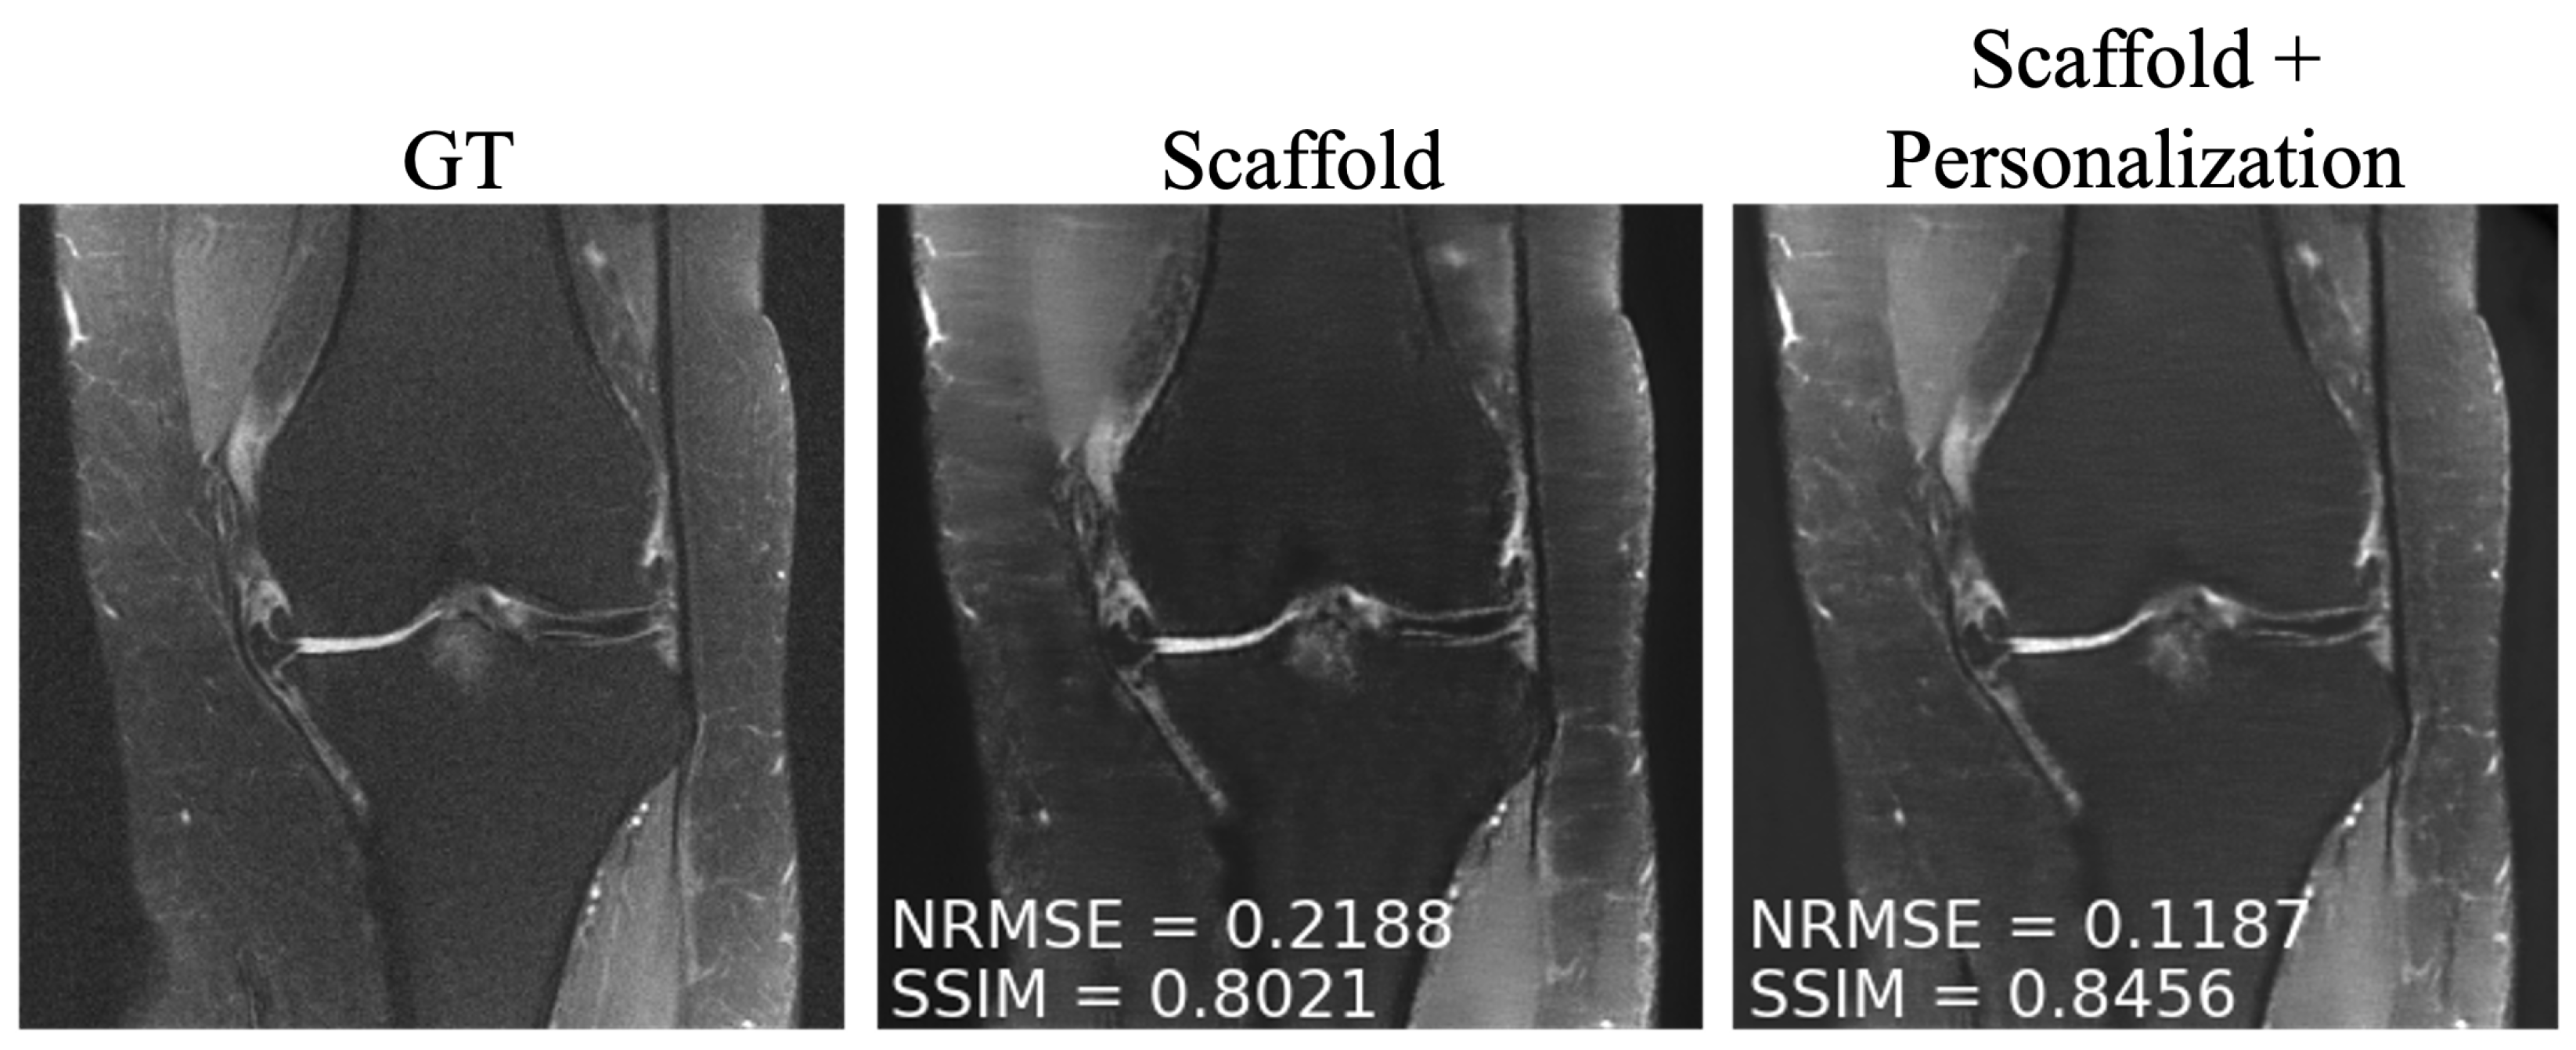

4.3. Personalization and Impact of Communication Budget

As mentioned in Section 3.4, after training, we personalized the model at each new site through fine tuning. We tuned two client-specific hyper-parameters ( r fine and N fine ) at one seen site (site 2) and two unseen sites (Stanford and NYU axial knee) using a five-fold cross-validation scheme on the available 50 local slices. The resulting hyper-parameters are displayed in Table 4. We picked site 2 (fastMRI, fat suppressed knee, 3T) from the sites present during training because it comes from the anatomy less represented among all clients, leaving room for more personalization gains similar to the unseen sites during training. Exemplar reconstructions are shown for one out-of-distribution client (Stanford abdomen) at 240 communication rounds and one in-distribution client (site 2) at four communication rounds in Figure 5 and Figure 6, respectively. In both cases, there is a substantial drop in performance for Scaffold, which is recovered after fine tuning.

Figure 5. Example reconstructions on a new client (Stanford) using (Center) only the pre-trained Scaffold model, (Right) Scaffold + personalization.

Bioengineering 10 00364 g005